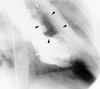

Fig. 1 Opacification of the aorta during left ventriculography shows a left sinus of Valsalva aneurysm (black arrows). The left main stem and the left anterior descending coronary artery are stretched and displaced upward (white arrows).